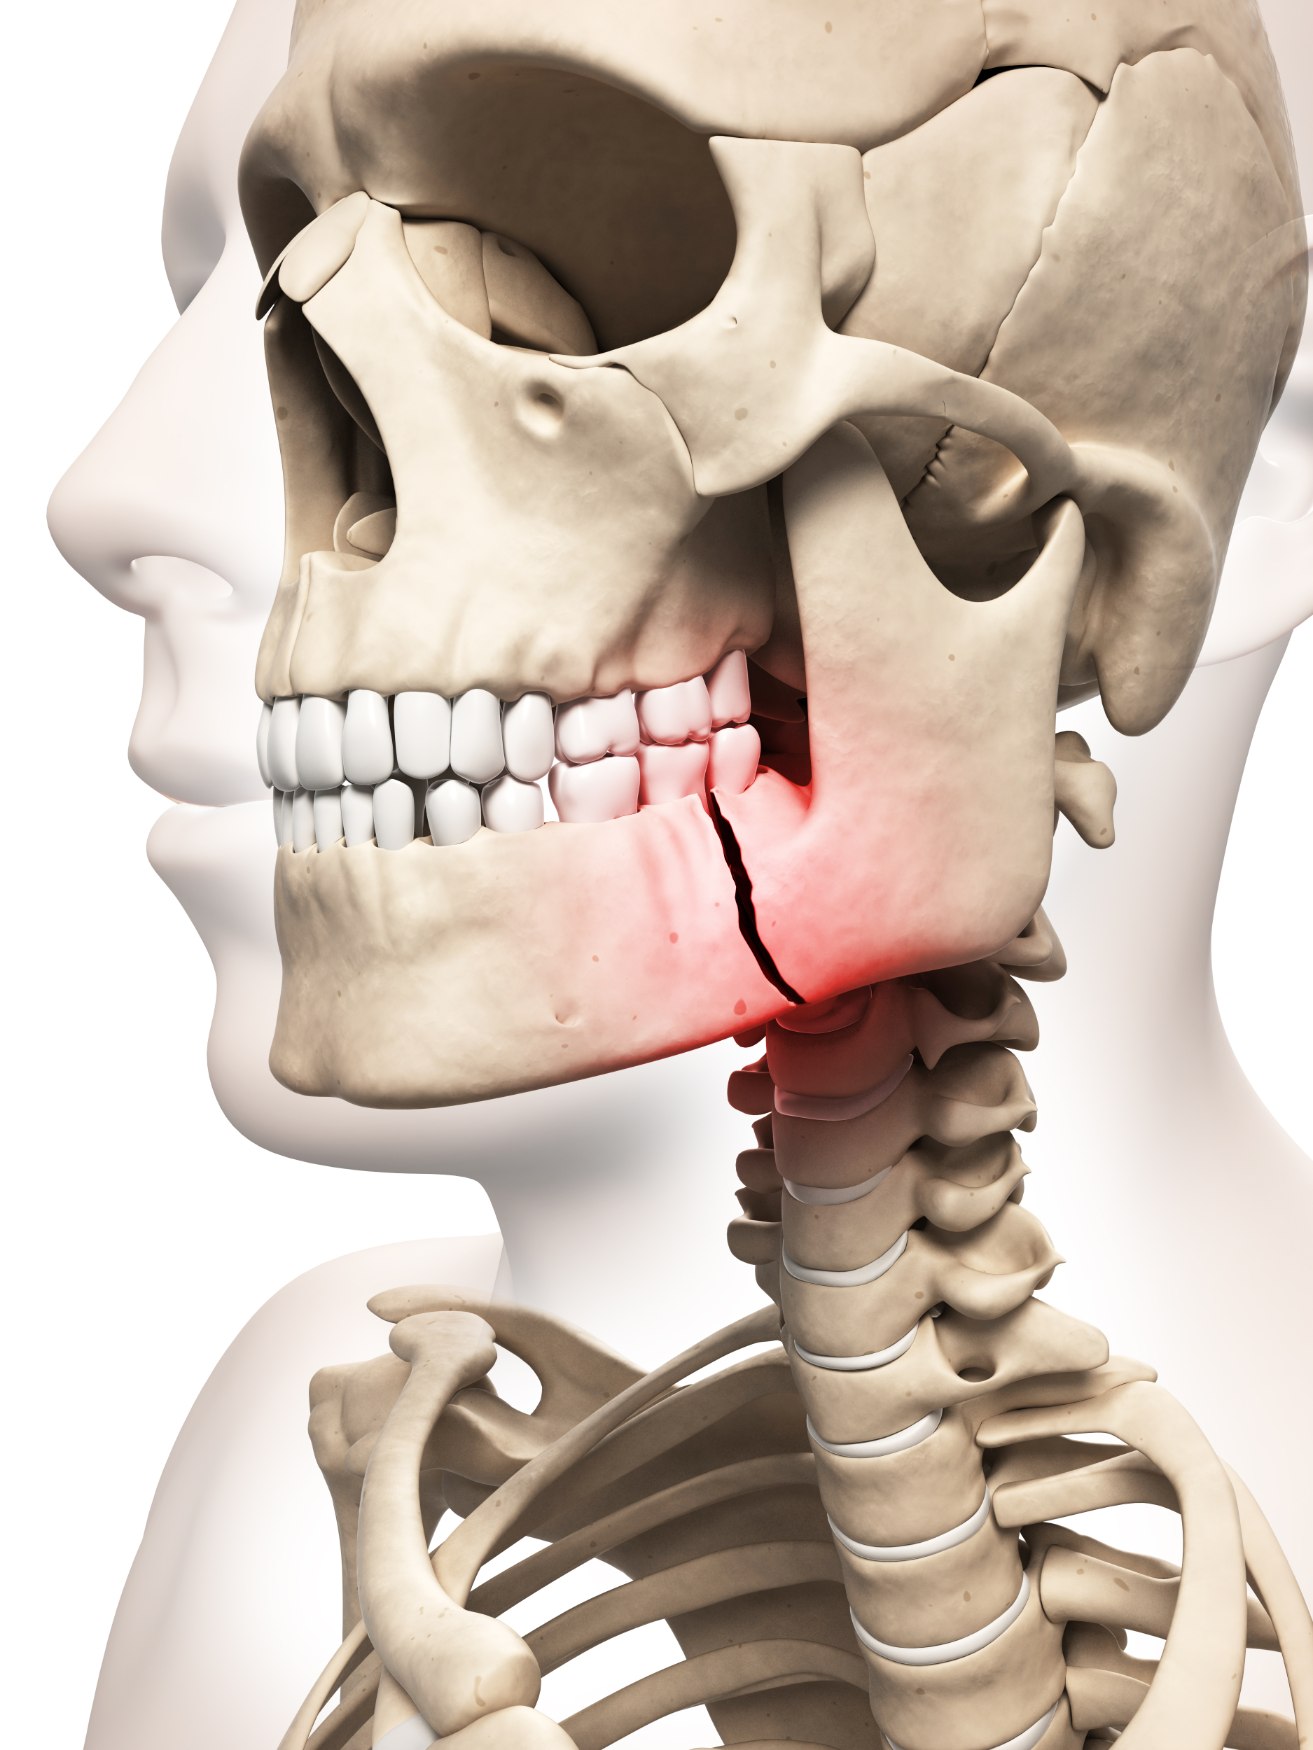

إصابات الوجھ الرضحیة ھي كسور عظام الوجھ مثل الفك السفلي (الفك السفلي) والفك

العلوي (الفك العلوي) والمدارات والحنك والأنف (الشق الأنفي وقمة الأنف) والأورام الوجنیة (عظام الخد) ومآخذ العین

والعظام الأمامیة ومجموعات من ھذه العظام. تحدث ھذه الأنواع من كسور الوجھ بسبب العدید من العوامل ، مثل حوادث

السیارات والریاضة. ھذه الإصابات یمكن أن تؤثر على القدرة على الرؤیة والتنفس والتحدث والبلع. إصابات الوجھ ھي

Traumatic facial injuries are the fractures of the facial bones like mandibles (lower jaw), maxillae (upper jaw), orbits, palates, noses (nasal notch and nasal crest), zygomas (cheekbones), eye sockets, frontal bones and combinations of these bones. These kinds of facial fractures occur due to many factors, such as car and sport-related accidents. These injuries can affect the ability to see, breathe, speak and swallow. Facial injuries are one of the most common serious injuries that occur when the facial bones are broken. Treatment often requires immediate hospitalisation and maxillofacial surgery. When maxillofacial fractures are complex or extensive, multiple incisions to expose the bones and a combination of wiring or plating techniques may be needed.